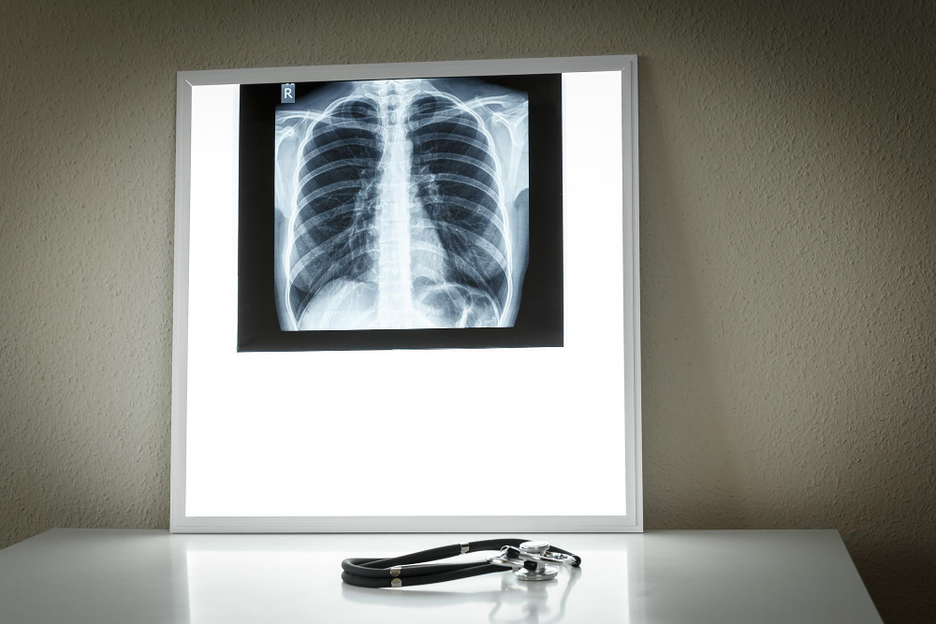

La doctora Rosario García-Campelo, jefa de Oncología Médica del Complexo Hospitalario Universitario de A Coruña, ha advertido de que los diagnósticos de cáncer de pulmón están ascendiendo entre un 4 y un 5 por ciento en mujeres en España y, de hecho, será la primera causa de muerte por cáncer en mujeres para 2025; mientras, la tendencia global de incidencia de esta enfermedad es a la baja.

Así se ha pronunciado en el marco del XIV Seminario de Periodistas organizado por la Sociedad Española de Oncología Médica (SEOM) y MSD bajo el título 'Diversidad y cáncer'. En cambio, en lo que respecta a los hombres, la tendencia se ha estabilizado en España. A nivel global, la experta ha resaltado que "por primera vez" la mortalidad por cáncer de pulmón está disminuyendo, aunque también aclara que este descenso es "menos pronunciado" en mujeres. De hecho, la oncóloga ha resaltado que la mortalidad por cáncer de pulmón desde 2003 e ha incrementado en 124 por ciento.

Por ello, ha incidido en la importancia de insistir en la prevención, ya que el 40 por ciento de los tumores se producen a causa de factores de riesgo evitables; de hecho, el 85 por ciento de las muertes por cáncer de pulmón se deben al tabaco. "Me preocupa qué está pasando con nuestros jóvenes. En 2021, 169.000 chavales empezaron a fumar, más chicas que chicos (56%)". Al hilo, ha alertado de que, cuando se traslada todo esto a la mujer, se ha descubierto que estas tienen un elevado riesgo de desarrollar cáncer de pulmón a menor exposición tabáquica.